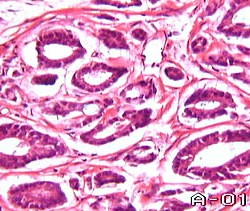

Фактов, указывающих на возможность автономного существования эпителиоцитов в стадии дисплазии, их прогрессирующего размножения и инфильтрации окружающих тканей, другими словами свидетельствующих об агрессивном, характерном для злокачественных опухолей поведении, нет. Поэтому существует реальная возможность в этом случае применять выжидательную тактику с постоянным мониторингом больных у которых в ткани предстательной железы обнаруживается дисплазия любой степени. Наиболее оправданным представляется динамический контроль ПСА, при тенденции нарастания которого выполняется повторная биопсия простаты. Вопрос о возможности лечения / химиопрофилактики диспластических состояний (PIN) находится в стадии изучения. В отличии от этого больные с диагностированной CIS, нуждаются в более энергичных лечебных мероприятиях. Дальнейшее развитие процесса онкогенеза приводит к инвазивному раку - стадии, в которой разворачивается вся гамма морфологических изменений. Она имеет достаточно четко очерченные критерии морфологической диагностики. Наиболее частый вариант - это аденокарцинома, которая составляет 95,7% всех гистогенетических групп РПЖ. Ее морфологическим проявлением является наличие комплексов опухолевых клеток, формирующих железистоподобные структуры. Составляющие их клеточные элементы проявляют выраженные в большей или меньшей степени признаки анаплазии. Ядра различной формы и величины - гиперхромны, уродливы и содержат различное количество ядрышек. Их интерфазный хроматин располагается неравномерно, глыбками. Ядерно-цитоплазматические соотношения нарушены в сторону ядра. Указанные признаки злокачественности нарастают вместе со степенью анаплазии. Именно нарастание степени анаплазии клеточных элементов опухоли или, другими словами, степени выраженности клеточного атипизма, является основополагающим диагностическим критерием степени злокачественности опухоли.

Поэтому, аденокарциномы I степени дифференцировки представляют из себя новообразования, состоящие из атипичных клеток, формирующих хорошо определяемые железистые структуры. В этом случае клеточный атипизм не достигает значительной степени выраженности, а основной показатель злокачественного роста - плоидность клеточных элементов опухоли, а именно, концентрация анеуплоидных (не кратных 2) клеточных элементов, не достигает 2%. По мере увеличения степени анеуплоидии нарастают и проявления клеточного атипизма, происходят определенные изменения в морфологическом строении ткани опухоли - появляется солидный компонент.

Поэтому, аденокарциномы I степени дифференцировки представляют из себя новообразования, состоящие из атипичных клеток, формирующих хорошо определяемые железистые структуры. В этом случае клеточный атипизм не достигает значительной степени выраженности, а основной показатель злокачественного роста - плоидность клеточных элементов опухоли, а именно, концентрация анеуплоидных (не кратных 2) клеточных элементов, не достигает 2%. По мере увеличения степени анеуплоидии нарастают и проявления клеточного атипизма, происходят определенные изменения в морфологическом строении ткани опухоли - появляется солидный компонент.